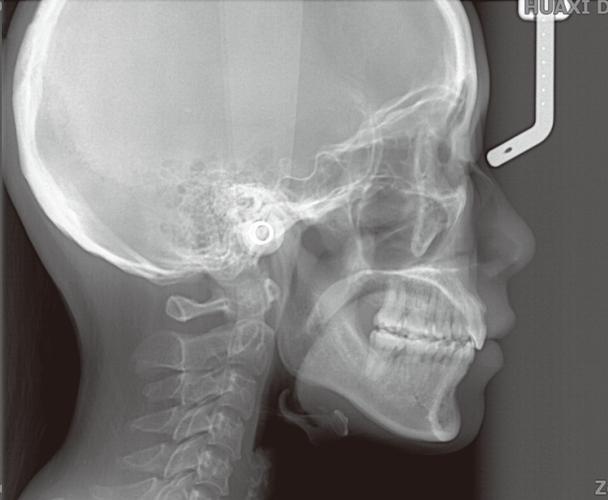

拍摄头颅侧位片需严格遵循标准化流程,以确保图像的准确性和可重复性,患者通常取站立位或坐位,头部自然放松,眶耳平面(外耳道上缘与眼眶下缘的连线)与地面平行,矢状面(通过鼻根和枕骨外粗隆的平面)与地面垂直,避免头部倾斜或旋转,X线球管中心线对准外耳道上方5cm处,拍摄距离一般为1.5-2米,以减少图像放大失真,儿童患者需配合固定装置(如头颅固定架)防止移动,必要时在家长协助下完成,整个拍摄过程快速、无创,辐射剂量极低(约0.007mSv),相当于乘坐飞机2小时所受的宇宙辐射,安全性高。

头颅侧位片在矫正中的核心应用

头颅侧位片的准确性依赖于拍摄标准化,任何头部倾斜、旋转均会导致测量误差,需由专业技师操作,对于生长发育期儿童,需结合手腕骨龄片评估生长潜力,头颅侧位片可定期拍摄(如每6-12个月)以监测骨骼变化,头颅侧位片需与全景片(观察牙根、牙槽骨)、口腔模型(分析牙弓形态)等联合应用,实现多维度评估,避免单一检查的局限性。